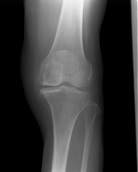

3.画像診断

- X-P所見(別紙参照):FTA左167°

- 骨折の特徴や手術法の特徴などを理解した上で、治療手技を考えていく必要がある。主なリスクは担当医に確認する

| 術前 | 術後 | 経過 |

![]() |

| FTA | 大腿骨と脛骨の長軸のなす大腿脛骨角。正常は約176度 |

| Mikulicz線 | 大腿骨頭中心から足関節中心を結ぶ下肢機能軸は立位での下肢荷重線を表し、正常では膝関節のほぼ中央を通過する |